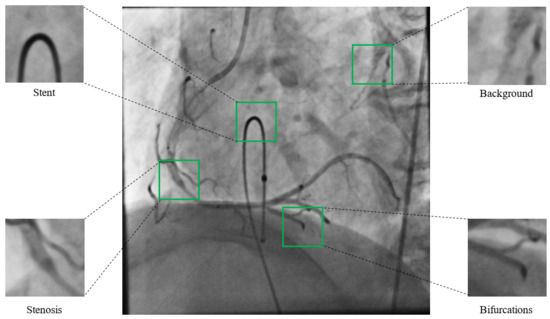

3.4. Datasets